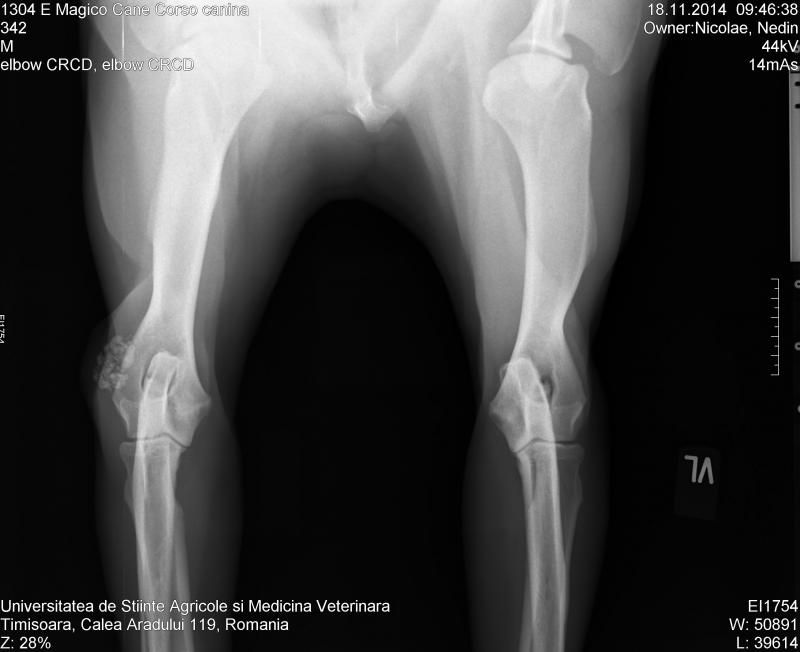

Wat zouden die 'vlokken' kunnen betekenen bij zijn elleboog?

Zouden eeltplekken zo duidelijk zichtbaar zijn op een röntgenopname?laeken schreef:Die hond ligt op harde ondergrond en die vlokken zijn zover ik kan bedenken dus eeltplekken van het liggen.

Maar daarom moet er dus gevoeld worden, aan de foto alleen heb je niks eigenlijk. En theoretisch moet het te voelen zijnInge O schreef:ja, klopt, het feit alleen dat het harde hoorn is maakt het nog niet zichtbaar op rx - een gecalcificeerde slijmbeurs op die plaats zou eventueel ook kunnen?Jeannettebo schreef:eigelijk zou het dan gecalcificeerd moeten zijn, wil het net zo wit tonen als bot.

ik zie in ieder geval geen relatie met het bot/gewricht.